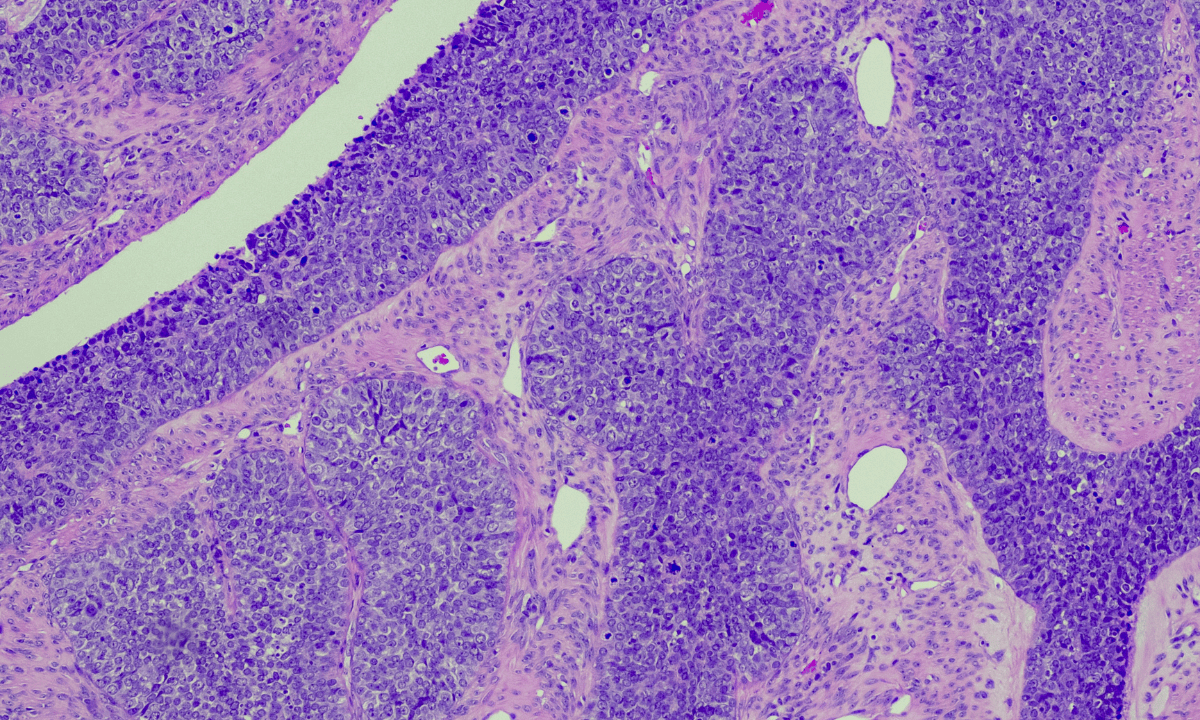

Epithelial ovarian cancer

This is the mostcommon type, accounting for about 90% of all ovarian cancers. These cancers begin in the thin layer of tissue that covers the ovary’s surface. Epithelial ovarian cancer most commonly develops in women over 50, particularly after menopause.

There are different subtypes of epithelial ovarian cancer, such as:

High-grade serous:

This is the most common subtype, accounting for more than 50% of cases of epithelial ovarian cancer.

High-grade serous carcinoma is most often diagnosed in women between the ages of 40 and 60.